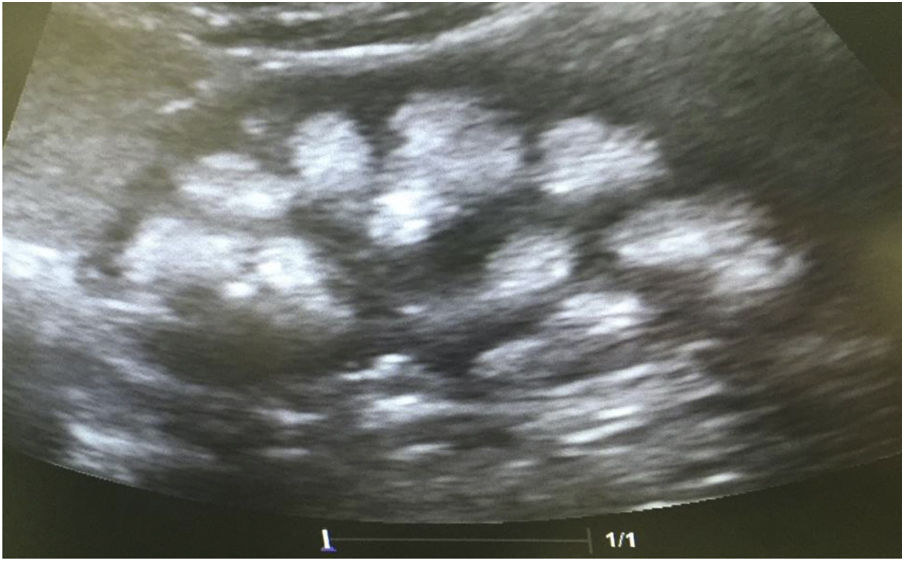

Casos clínicosCaso 1Paciente femenino de 4 años y 3 meses de edad. Peso al nacer 2.800g, talla 48cm y Apgar 8/9. Como antecedente presenta avidez por el agua y la sal. Poliuria y nicturia en la etapa de lactante. Fue hospitalizada en 11 ocasiones por fiebre sin foco aparente. A los 20 meses de edad fue diagnosticada de herpes zóster y tratada con aciclovir durante 7 días; a continuación, presentó un cuadro diarreico, deshidratación moderada y flacidez generalizada con incapacidad para caminar. Fue hospitalizada en el Hospital General de Zona con la sospecha de síndrome de Guillain-Barré; su peso era 9,5kg y la talla 82cm (ambos en percentil 10). Se observó hipopotasemia (2,5mEq/l) y acidosis metabólica. Tras instaurarse tratamiento intravenoso y la corrección del desequilibrio hidroelectrolítico, mejoró la fuerza muscular logrando la deambulación. Sin embargo, persistía la acidosis metabólica hiperclorémica. Los datos bioquímicos y los hallazgos de la ecografía aparecen en la tabla 2 y la figura 2, respectivamente. La valoración audiológica no mostró datos de hipoacusia neurosensorial. El estudio oftalmológico fue normal. Se realizó una prueba de acidificación urinaria con bicarbonato de sodio y acetazolamida según un protocolo descrito previamente (prueba de pCO2 urinaria máxima)11–13. La prueba se realizó sin complicaciones, fue bien tolerada y se consideró valida al conseguirse una bicarbonaturia superior a 80mEq/l. Se cuantificó una pCO2 urinaria máxima de 80mmHg a los 60min (anormal<70mmHg) (tabla 3). Se comprobó que la paciente es portadora de la misma mutación que su madre. Después de 3 años de tratamiento con álcalis ha mejorado el peso y la talla, a saber, 16,5kg (percentil 47) y 103cm (percentil 34), respectivamente. En la actualidad recibe tratamiento con citrato de potasio (4,5mEq/kg/día) con lo que ha remitido la hipercalciuria. La TA es normal (89/59mmHg).